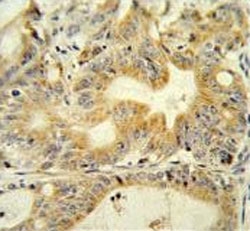

IHC testing of FFPE human colon carcinoma tissue with DcR3 antibody. HIER: steam section in pH6 citrate buffer for 20 min and allow to cool prior to staining.